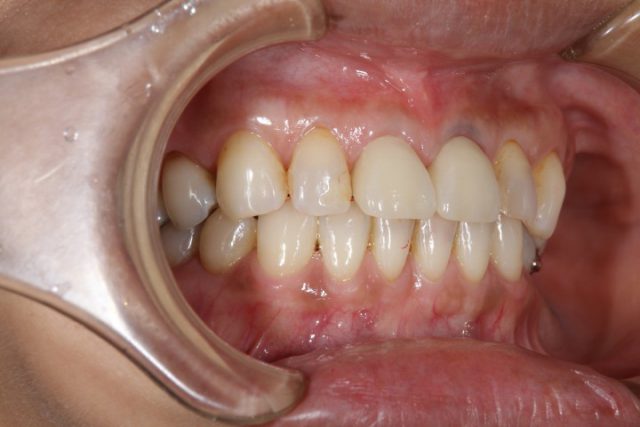

施術後

今回のように以前に施術した詰め物が変色したり、場合によっては欠損してしまったりの時に思い切ってオールセラミックによる施術を検討されてはいかがでしょうか。

歯のストレスというのは小さなことに思えますが、患者様のほとんどが施術後に大きなストレスだったと気づかれます。是非一度口の中にストレスがないかどうかセルフチェックしてみてくださいね!